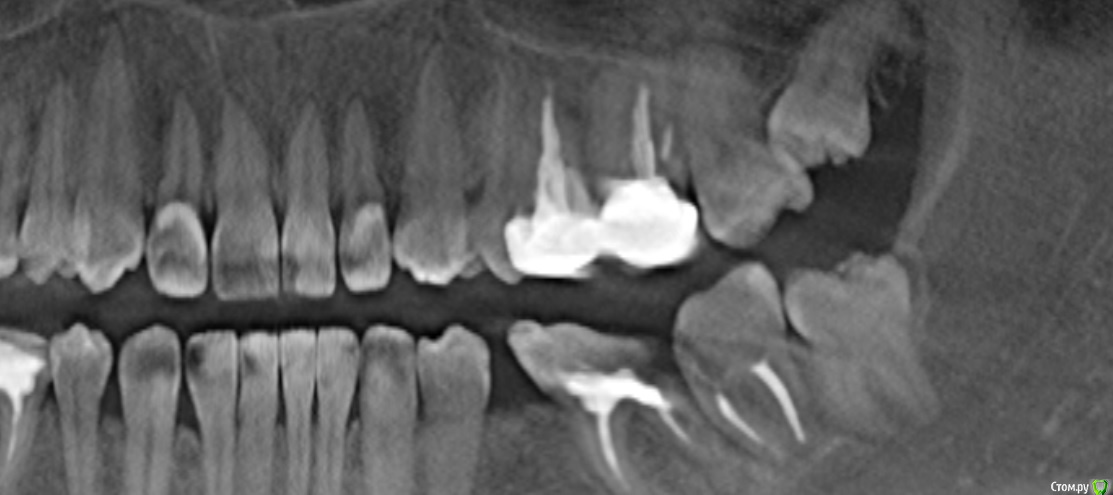

Margo03 Опубликовано 13 апреля, 2015 Поделиться Опубликовано 13 апреля, 2015 Добрый вечер! Интерисует вопрос , можно ли поставить коронку на 7 нижний зуб с левой стороны, если стенка зуба откололась в ровень с десной? Есть ли какие-то методы востановления зуба для дальнейшего протезирования? Или зуб только под удаление и имплант? На 6 -ку рядом точно не поставить , хотелось бы всё-таки один зуб сохранить на этой стороне. Заранее спасибо за ответ! Ссылка на комментарий

Гарриевич Опубликовано 13 апреля, 2015 Поделиться Опубликовано 13 апреля, 2015 (изменено) прицельный снимок нуженпредварительно по 7ке: можно нарежте пару срезов в области 7 зуба Изменено 13 апреля, 2015 пользователем Гарриевич Ссылка на комментарий

Vadim09 Опубликовано 13 апреля, 2015 Поделиться Опубликовано 13 апреля, 2015 К сожалению, по снимку нельзя увидеть язычную и щечную стороны, оценить, надо смотреть в кресле. Ссылка на комментарий